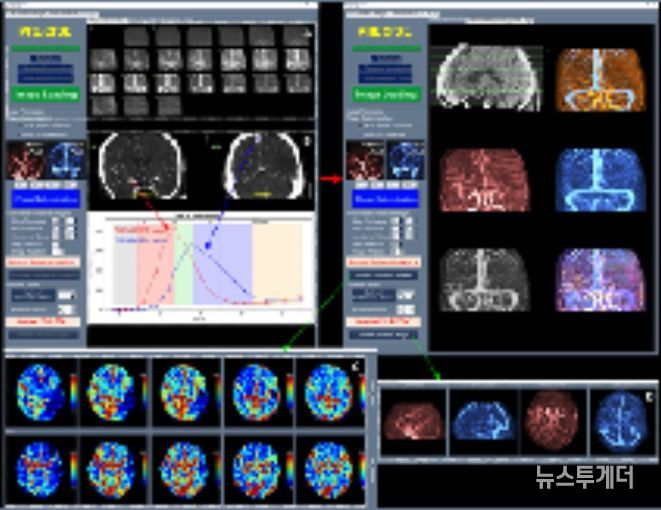

이와 함께 허혈성 뇌혈관 질환 환자를 대상으로 혈관재개통 치료가 필요한 환자 선별을 지원하는 소프트웨어 등 다양한 진단·치료 보조 AI 의료기기들이 혁신의료기기로 지정됐다.